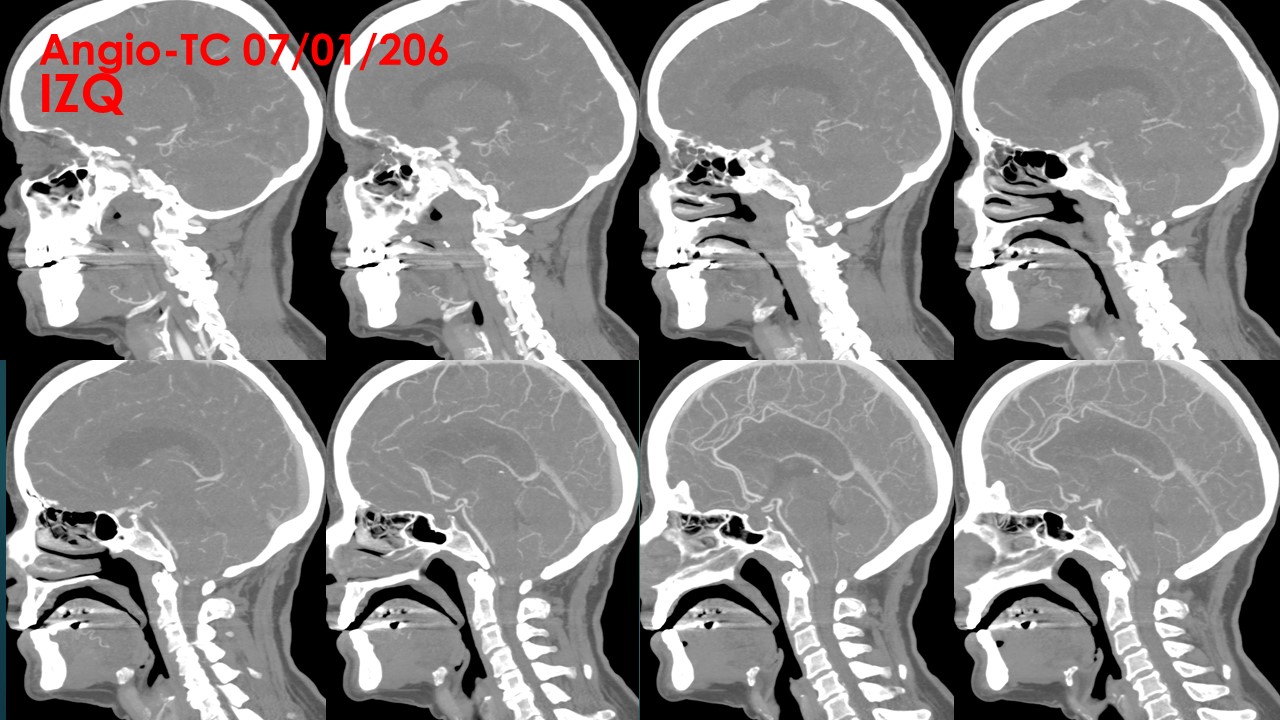

ANGIO TC:

Troncos supraorticos permeables, sin variantes anatómicas reseñables.

Origen fetal de ambas arterias cerebrales posteriores.

A nivel de la arteria carótida supraclinoidea derecha, entre la salida del ACoP (ACP) ipsilateral y la ACA derecha se observa una imagen de adición opacificada de aspecto nodular, de aproximadamente 11 mm x 8 mm, compatible con aneurisma, probablemente responsable de la hemorragia actual. A nivel de la arteria carótida supraclinoidea izquierda se observa otra imagen de características similares de 7 mm x 4.5 mm, compatible con aneurisma de dicha arteria.

No se visualizan otras dilataciones aneurismáticas a nivel intracraneal.

No se observan estenosis valorables en sistema arterial intra ni extracraneal.